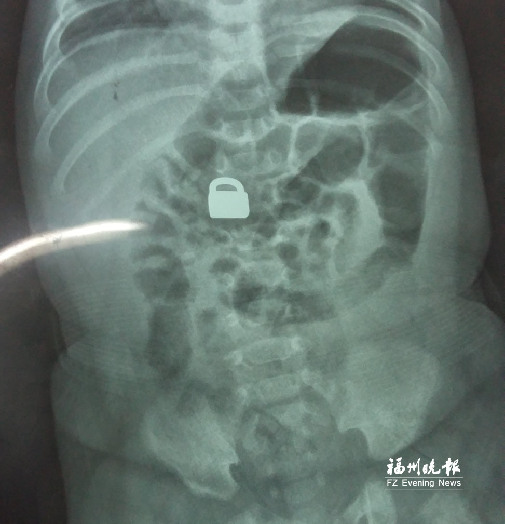

7.25龍巖當(dāng)?shù)蒯t(yī)院拍的X光片顯示,平安鎖在寶寶體內(nèi)。

這名60天大的“神奇寶寶”來自龍巖,哥哥也只有兩歲。7月25日,兄弟倆的媽媽突然發(fā)現(xiàn)寶寶胸前掛著的平安鎖不見了,便問小哥哥是否看到弟弟的平安鎖。小哥哥回答,他把平安鎖塞到弟弟嘴里了。媽媽趕緊檢查寶寶嘴巴,沒有發(fā)現(xiàn)平安鎖。雖然寶寶沒有任何癥狀,但媽媽還是帶著他去當(dāng)?shù)蒯t(yī)院檢查。拍片結(jié)果顯示,平安鎖真的在寶寶體內(nèi)。

“X光片顯示,那是一把1.5厘米×0.9厘米的平安鎖,有指甲蓋大小,已經(jīng)到了寶寶的小腸處?!?月28日,陳惠萍見到寶寶時(shí),吃了一驚,“他真的好小,被抱在媽媽懷里,眼睛微微睜開,我估計(jì)他的世界還是混沌的,沒想到就已經(jīng)接受了這么大的挑戰(zhàn)?!?/p>